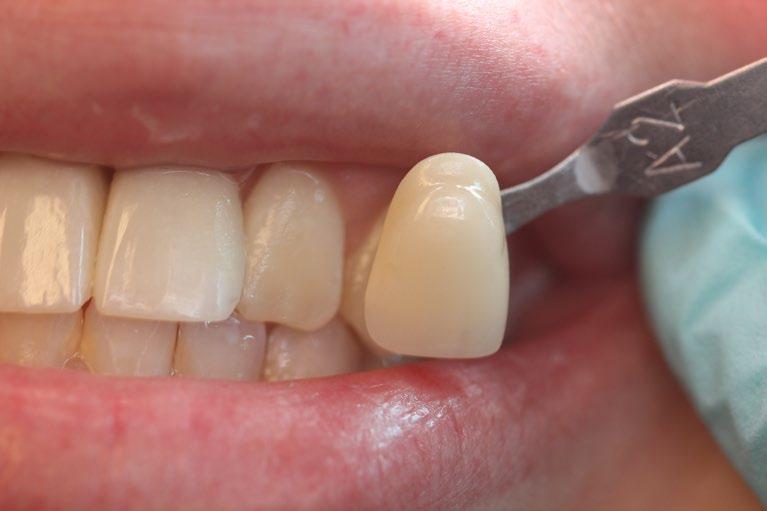

Creating a New Look with Dental Implants

One of the most significant advantages of dental implants is their ability to restore a natural-looking smile. They are customdesigned to match the natural color and shape of the patient’s existing teeth, blending seamlessly into the mouth. This can dramatically improve a person’s appearance, making them look younger and healthier. For many, this can lead to a renewed sense of self-esteem and vitality, particularly important as they age.

The Impact on Confidence

Beyond aesthetics, the functionality provided by dental implants plays a crucial role in boosting confidence among older adults. With age, many individuals face dental issues such as tooth loss, which can lead to difficulties in speaking and eating. Dental implants restore these capabilities to their fullest potential, allowing people to enjoy a variety of foods and speak clearly and confidently without the worry of slipping dentures.